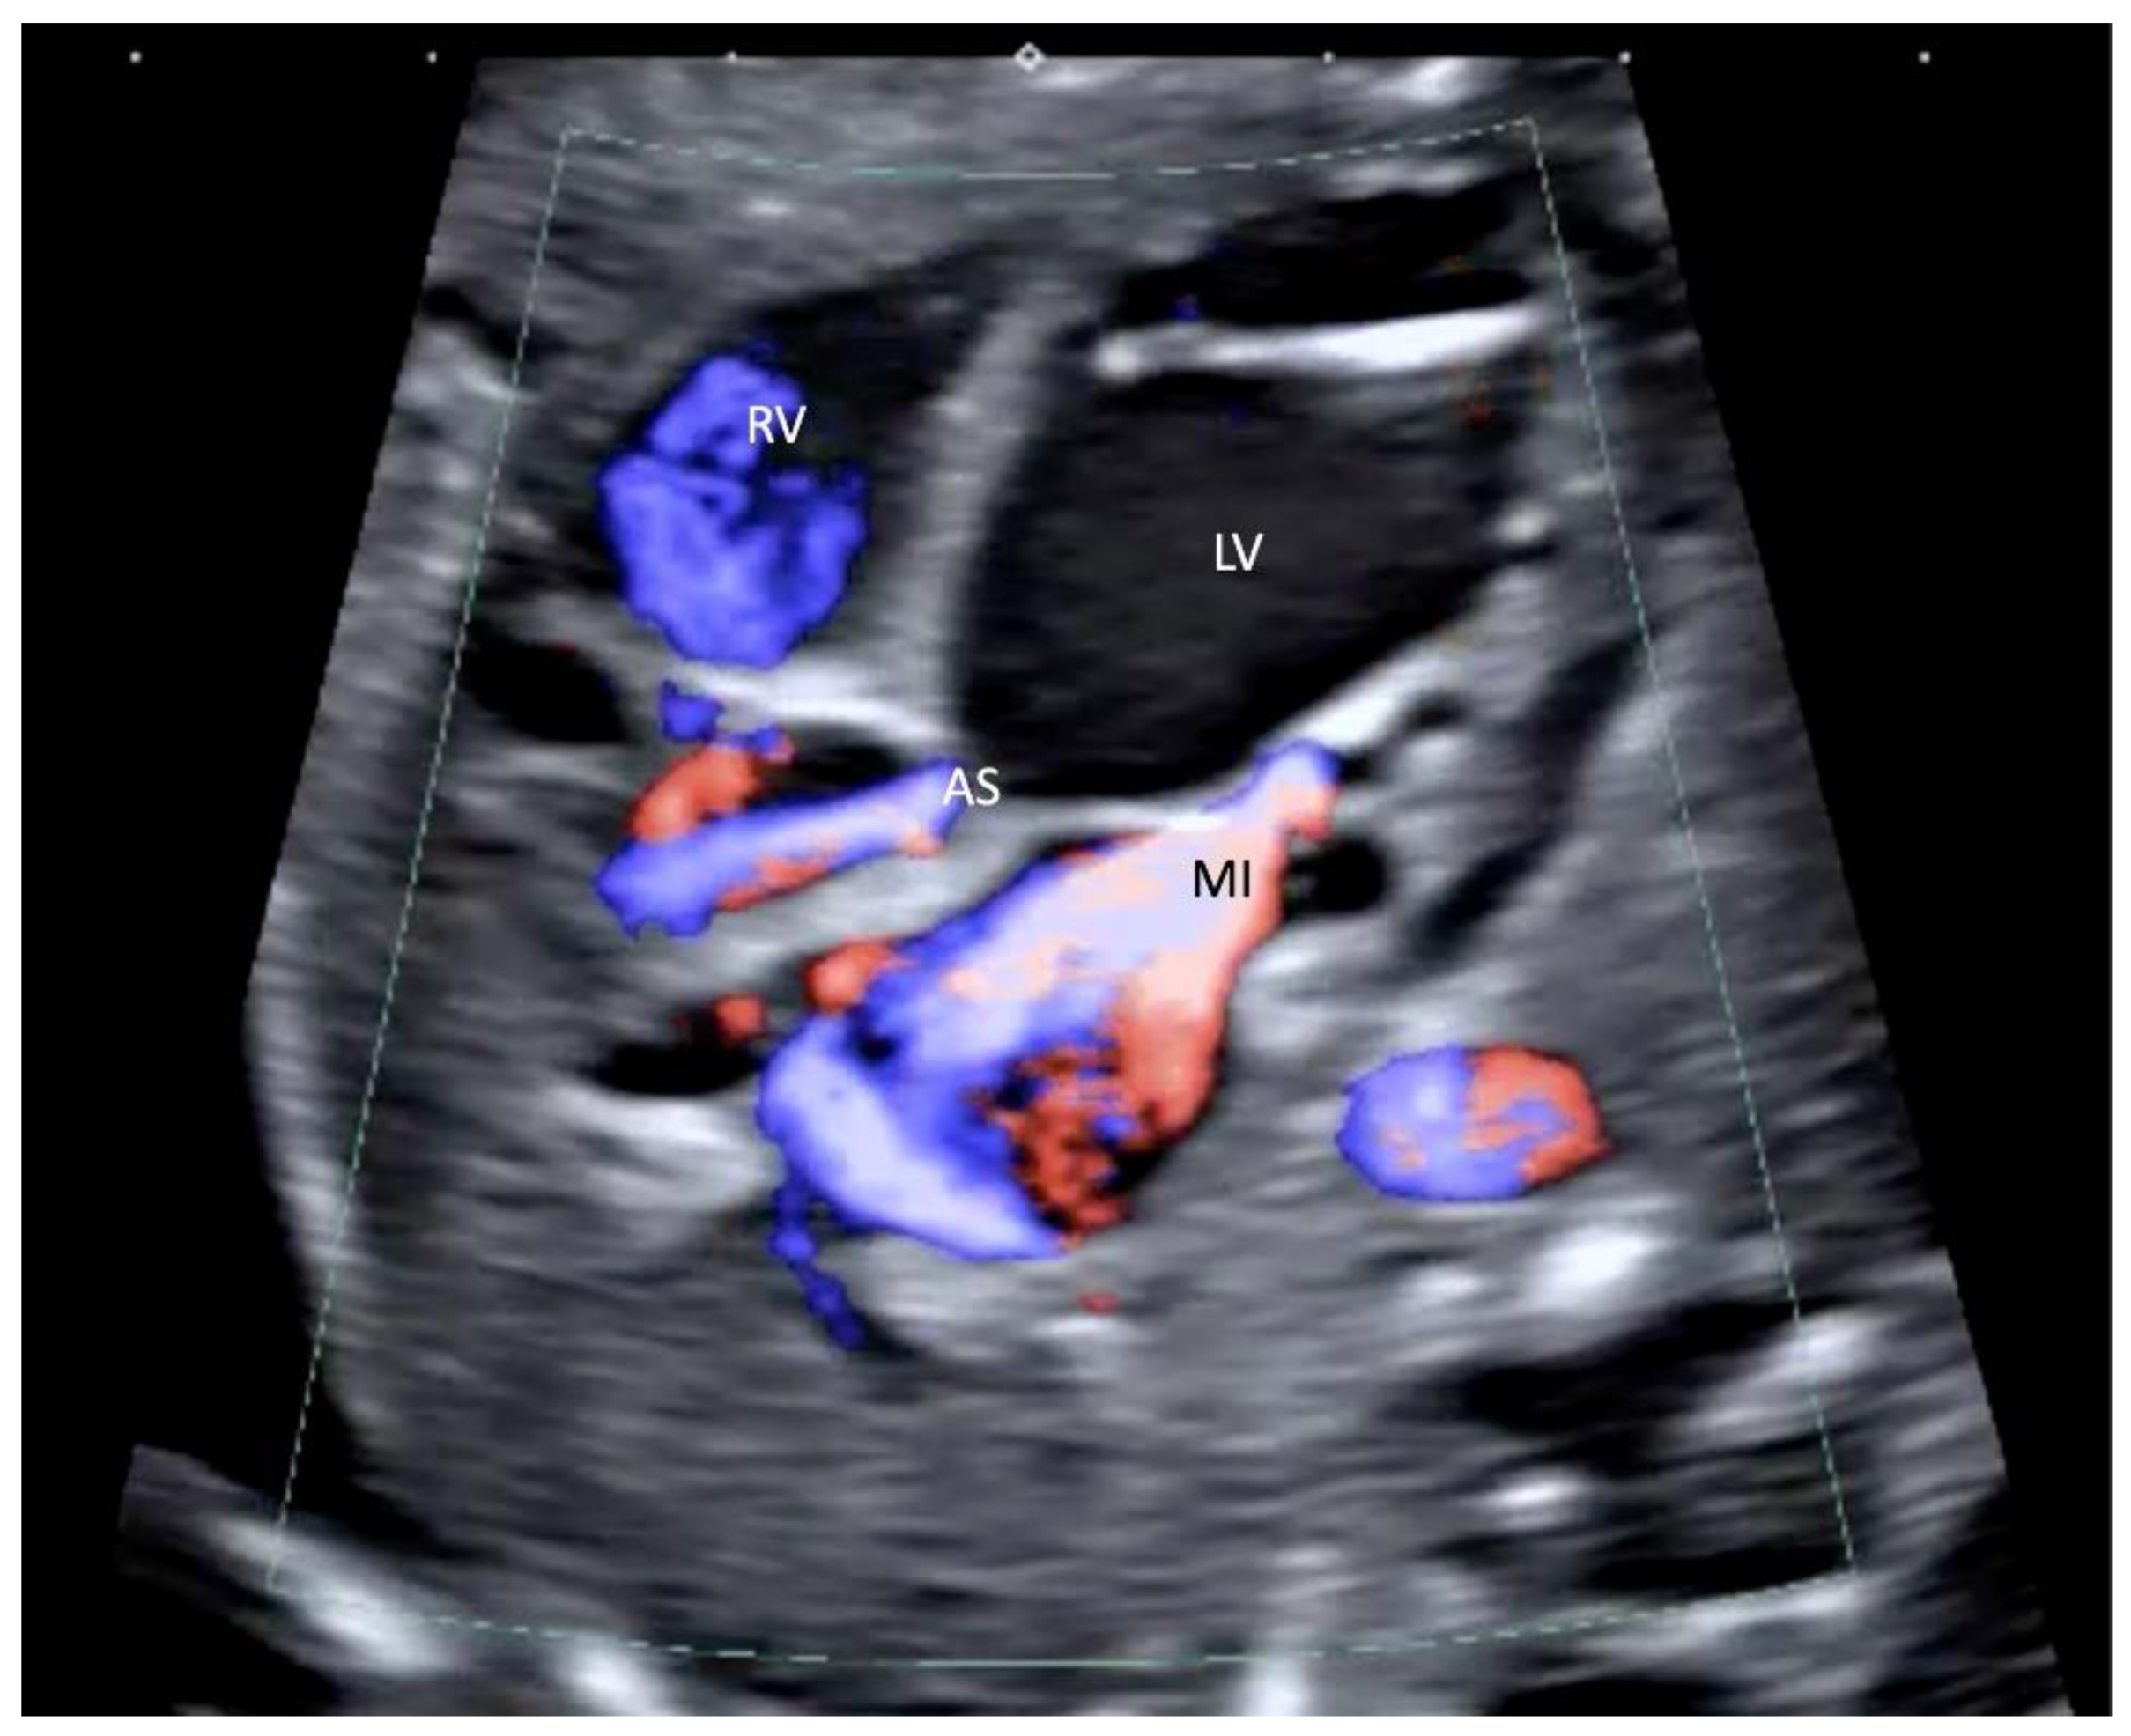

2.2. Procedure

2.3. Outcome